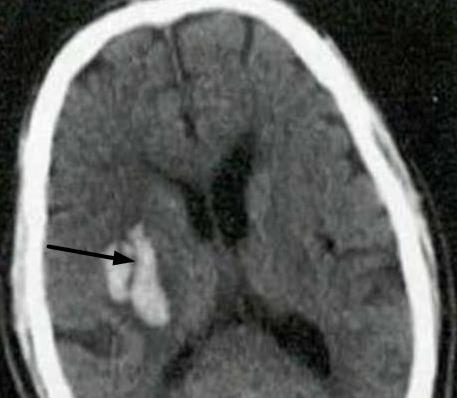

• 神经内镜下不同出血部位高血压脑出血血肿清除手术技巧探讨

摘要:目的 探讨神经内镜下不同出血部位高血压脑出血(HCH)血肿清除手术技巧及其治疗效果。方法 选取2022年5月-2024年1月该院收治的HCH患者101例,根据CT结果,将患者按照脑出血部位分为脑叶出血组(n = 43)和基底节区出血组(n = 58)。该研究采用Pearson法,分析脑微循环指标与美国国立卫生研究院卒中量表(NIHSS)评分、简易智能精神状态检查量表(MMSE)评分和日常生活能力Barthel指数(BI)评分间的相关性;基于广义估计方程,分析神经内镜下血肿清除术对不同出血部位患者脑微循环指标的改善效果。基于双重差分方程模型,分析神经内镜下血肿清除术对不同出血部位患者NIHSS评分、MMSE评分和BI评分的改善效果,并将基线指标纳入模型作为控制变量。结果 基底节区出血组手术时间明显长于脑叶出血组,NIHSS评分、MMSE评分、BI评分、平均通过时间(MTT)、脑血流量(CBF)、脑血容量(CBV)和平均动脉压(MAP)治疗前后差值变化明显小于脑叶出血组,差异均有统计学意义(P < 0.05);两组患者并发症发生率比较,差异无统计学意义(P > 0.05);相关分析结果显示,MTT与NIHSS评分呈正相关,MTT与BI评分和MMSE评分呈负相关,CBF、CBV和MAP与NIHSS评分呈负相关,CBF、CBV和MAP与BI评分和MMSE评分呈正相关,差异均有统计学意义(P < 0.05);广义估计方程分析结果显示,脑叶出血组MTT、CBF、CBV和MAP改善情况明显优于基底节区出血组,差异均有统计学意义(P < 0.05);双重差分方程模型分析结果显示,年龄增大、MTT延长和发病到手术时间的延长对NIHSS评分产生正影响(B = 0.884、1.291和0.758,P < 0.05),对MMSE评分产生负影响(B = -1.014、-1.569和-0.821,P < 0.05);MTT延长对BI评分产生负影响(B = -0.973,P < 0.05);CBV、CBF和MAP的升高对NIHSS评分产生负影响(B = -0.841、-0.767和-1.213,P < 0.05),对MMSE评分和BI评分产生正影响(MMSE:B = 0.932、0.738和0.874;BI:B = 0.897、0.751和0.842,P < 0.05)。结论 神经内镜下血肿清除术通过调节HCH患者的MTT、CBF、CBV和MAP等指标,可改善HCH患者的NIHSS评分、MMSE评分和BI评分,且脑叶出血患者改善效果明显优于基底节区出血患者。